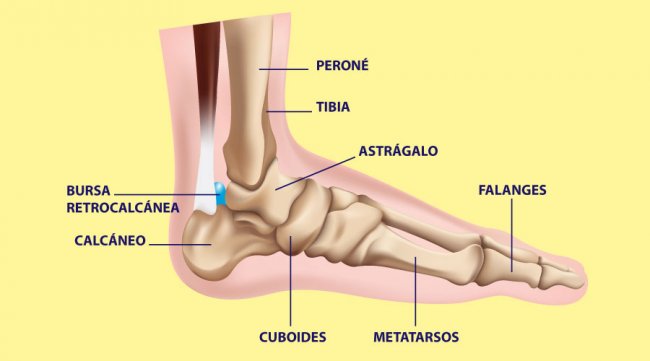

Fracturas La articulación del tobillo une la pierna con el pie y es la que ...